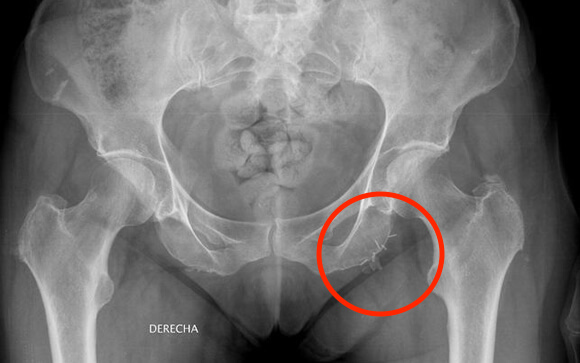

Radiografía del abdomen de una paciente con restos de agujas de mala calidad:

«El problema es que las elecciones son cada cuatro años, y los políticos no miran más allá de ese espacio de tiempo»El vicepresidente primero de esta agrupación de pacientes, Aureliano Ruiz expone, en declaraciones a ConSalud.es, que muchos pacientes se ven obligados a utilizar agujas ?de mala calidad? que, incluso a menudo, llegan a romperse quedándose dentro del abdomen del paciente. Además, advierten del dolor que provocan durante su uso.